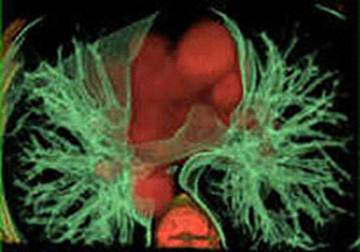

более плотных участках. (рис. 2)

Другим примером является прямая радионуклидная

цистография. Методика исследования включает катетеризацию уретры, ретроградное

заполнение мочевого пузыря физиологическим раствором хлорида натрия, смешанного

с меткой, и получение с помощью гамма-камеры изображений области мочевых путей

во время заполнения пузыря, в момент мочеиспускания и после него. Полученное

изображение приведено на Рис. 3.

Рисунок 3 - Радионуклидная диагностика мочевого

пузыря.